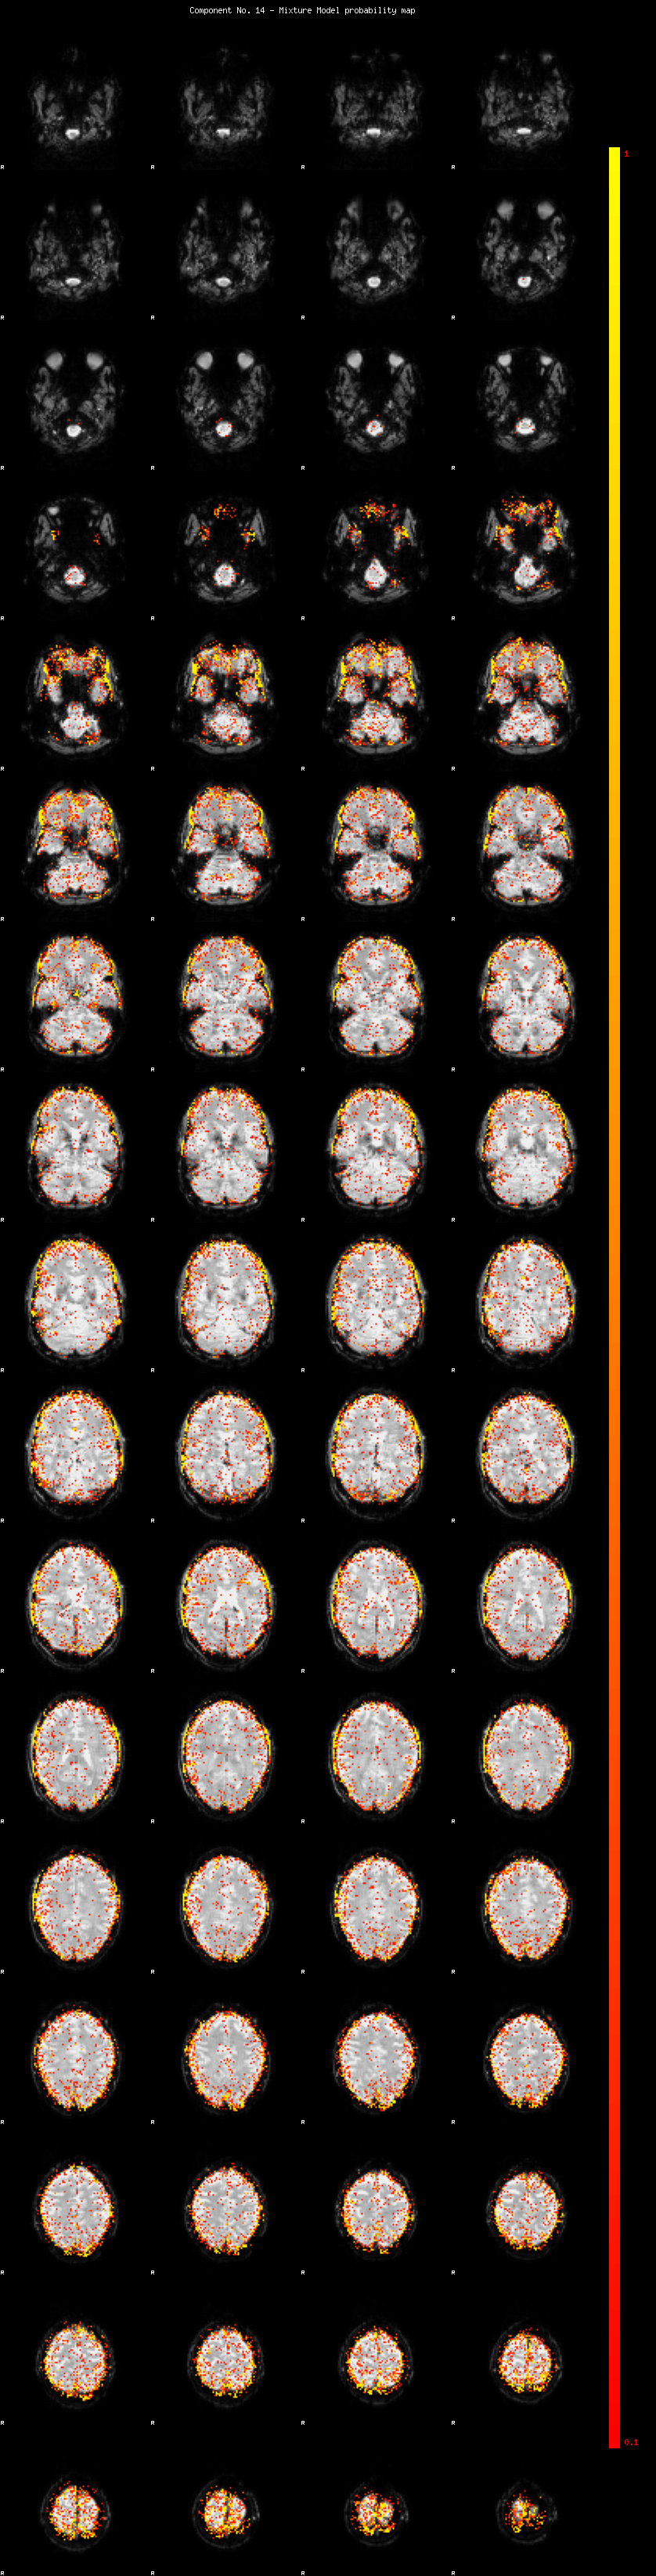

IC_14 Mixture Model fit

Means : 0.000000 3.667427 -2.853056

Vars : 1.000000 6.336244 1.668933

Prop. : 0.906222 0.053851 0.039927